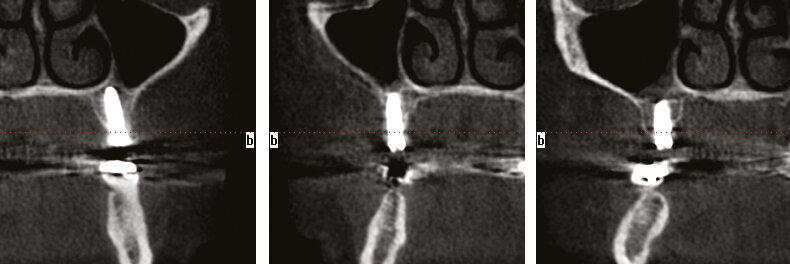

Figs.18-20: CT slices to confirm proper placement.

Fig.21: 1 year post x-ray showing bone formation over the top of the Axiom REG implants.